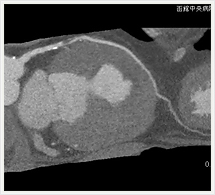

画像紹介

CTでは輪切り像の他にも立体的な画像(3D画像)を作成することもできます。そのためにはより細かくキレイな画像を撮影しなければなりません。当院では64列CTを導入しており、キレイな画像をより細かく撮影することができます。その画像を元に3D画像を作成することによって、より正確な手術のシミュレーションが可能になります。実際に手術をしたときの様子が、手術をする前に画像として見らます。外科系の手術には欠かせない技術となっておりますが、内科系でも血管内手術にも多く利用されております。

当診療放射線技術科では毎日各診療科に対して、その手術に最適な3D画像を提供しております。

以下にその3D画像を一部分紹介します。

胸部大動脈

胸部大動脈(赤)、奇静脈(青)、脊椎結核(黄)